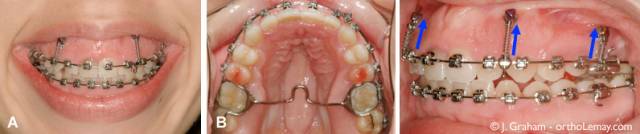

· 下图(A,B,C)是患者刚转诊到Graham医生这里时的样子。(D)图,是在使用了TAD微型种植钉后,笑露牙龈有所缓解的相片。

虽然经历过此阶段治疗后,咬合及牙列情况比较令人满意,但微笑时依然露出大片牙龈,这是因为此种矫正方式本来应该在外科手术下进行(实际上并未进行)。治疗依然是要减少微笑时露出牙龈的面积。

使用微型种植钉抬高牙列之前,咬合看起来还不错。

4颗微型种植钉提供了抬高的力,是为了抬高上颌牙列,然后降低微笑时露牙龈的度。